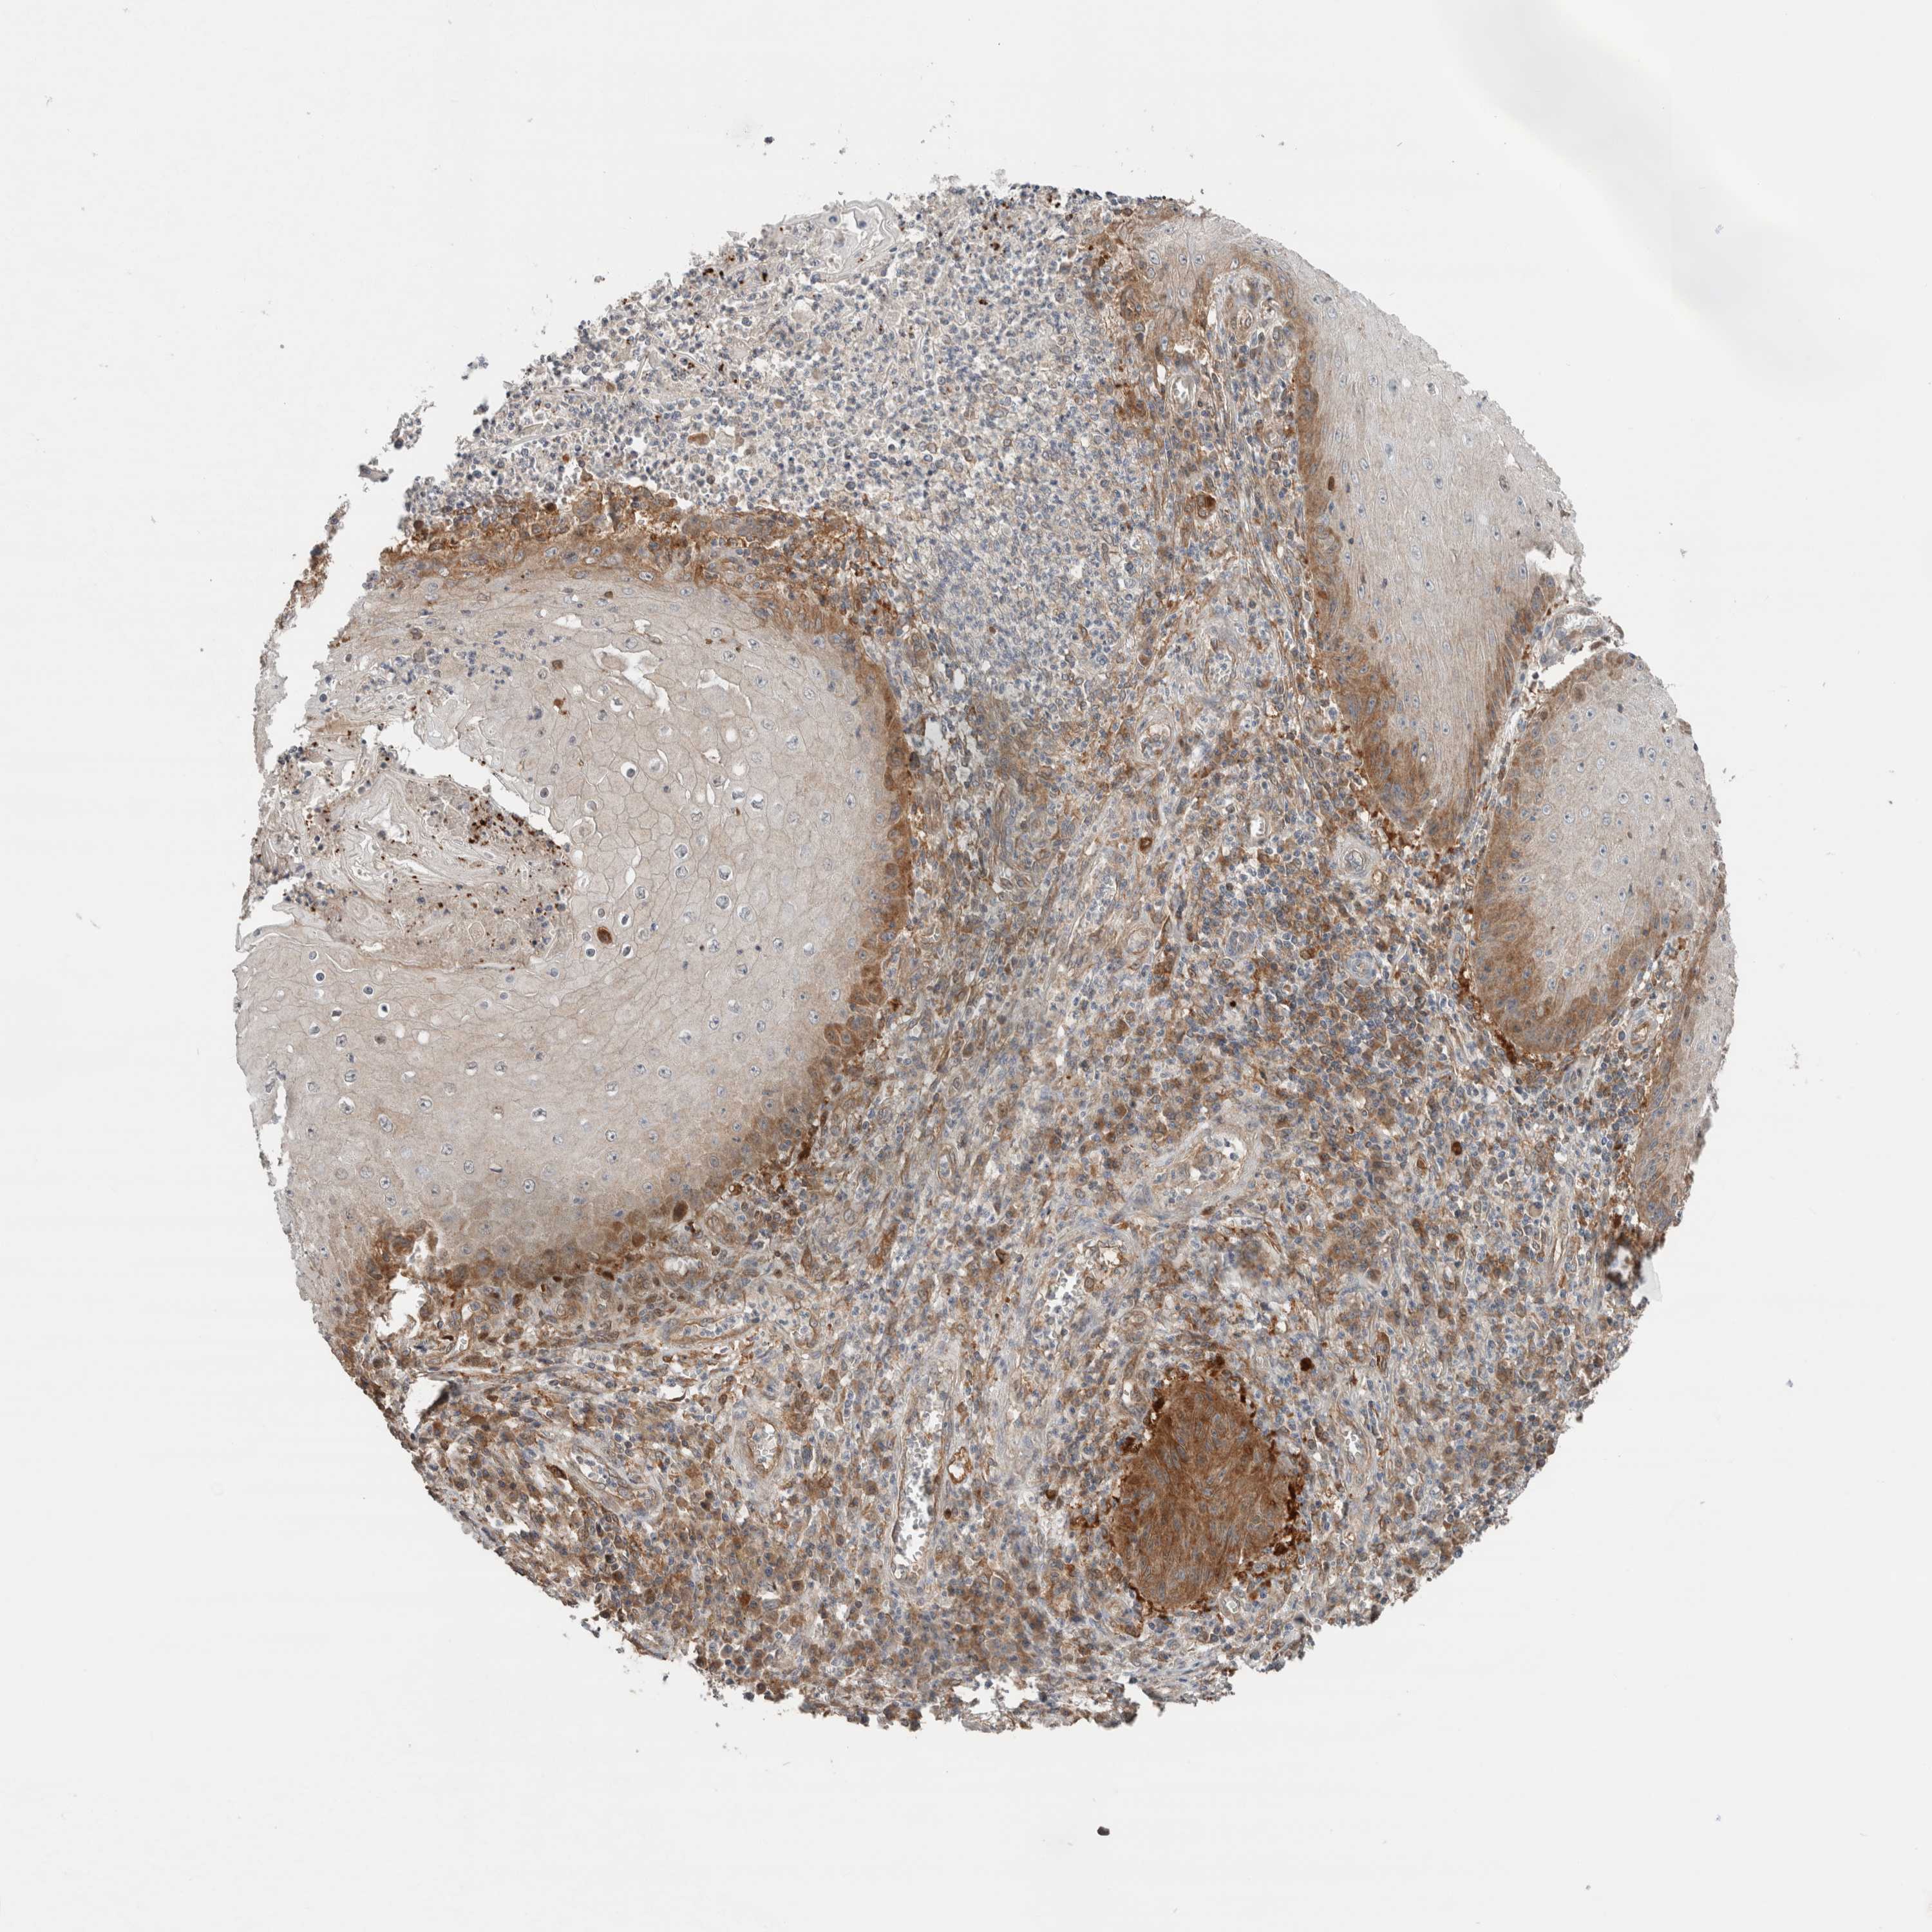

SKIN CANCER - Protein expressioni

A mouse-over function shows sample information and annotation data. Click on an image to view it in a full screen mode. Samples can be filtered based on level of antibody staining by selecting one or several of the following categories: high, medium, low and not detected. The assay and annotation is described here.

Antibody stainingi

Antibody staining in the annotated cell types in the current human tissue is reported as not detected, low, medium, or high, based on conventional immunohistochemistry profiling in selected tissues. This score is based on the combination of the staining intensity and fraction of stained cells.

Each image is clickable and will lead to virtual microscopy that enables deeper exploration of all samples and also displays staining intensity scores, fraction scores and subcellular localization as well as patient and tissue information for each sample.

HPA030419

HPA030420

HPA030422

CAB025196

CAB080286

CAB080287

Staining

High

Medium

Low

Not detected

Intensity

Strong

Moderate

Weak

Negative

Quantity

>75%

75%-25%

<25%

None

Location

Nuclear

Cytoplasmic/membranous

Cytoplasmic/membranous,nuclear

Basal cell carcinoma

Squamous cell carcinoma, NOS

Squamous cell carcinoma, metastatic, NOS